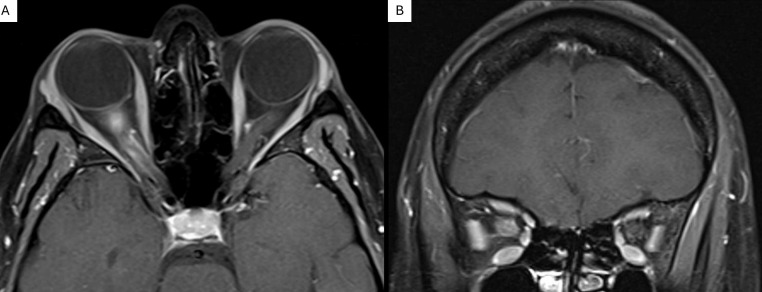

Observations: A woman presented with unilateral retro-orbital pain, mildly decreased vision, and optic disc edema with new-onset aphthous ulcers. Color vision was preserved, and no visual field deficits were noted. Diagnostic imaging demonstrated retrobulbar optic nerve enhancement, with genetic testing revealing HLA-B35 positivity. Treatment with high-dose oral steroids for 3 days resolved all symptoms, and the patient remained stable for at least 2 months.